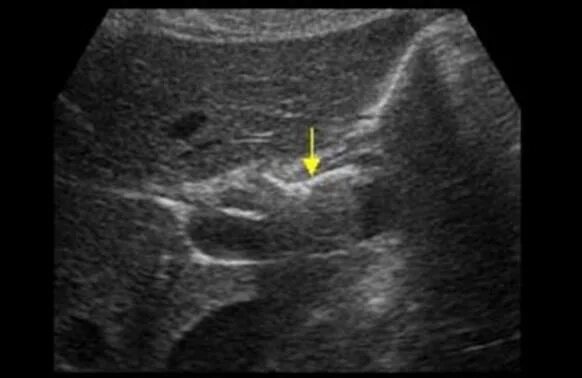

Образование анэхогенной структуры